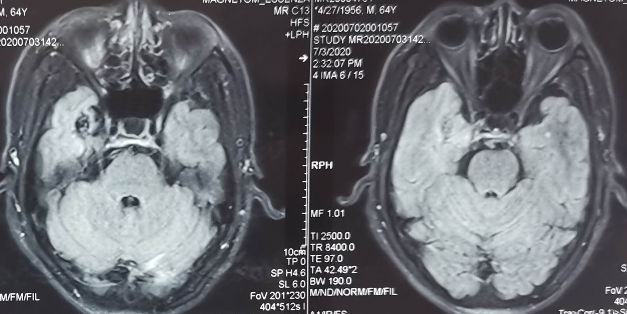

外院头颅CT示右侧颞叶钙化灶,头颅MRI示见右侧颞叶流空信号,考虑动静脉畸形。

入院后脑血管造影检查提示:右侧颞叶动静脉畸形,由右侧大脑中动脉两分支血管参与供血,右侧大脑后动脉一分支血管参与供血,畸形团大小约1.1*1.3cm,通过侧裂静脉经皮层静脉引流入上矢状窦前部;并可见右侧大脑后动脉供血畸形团的分支血管血流相关性动脉瘤两枚。